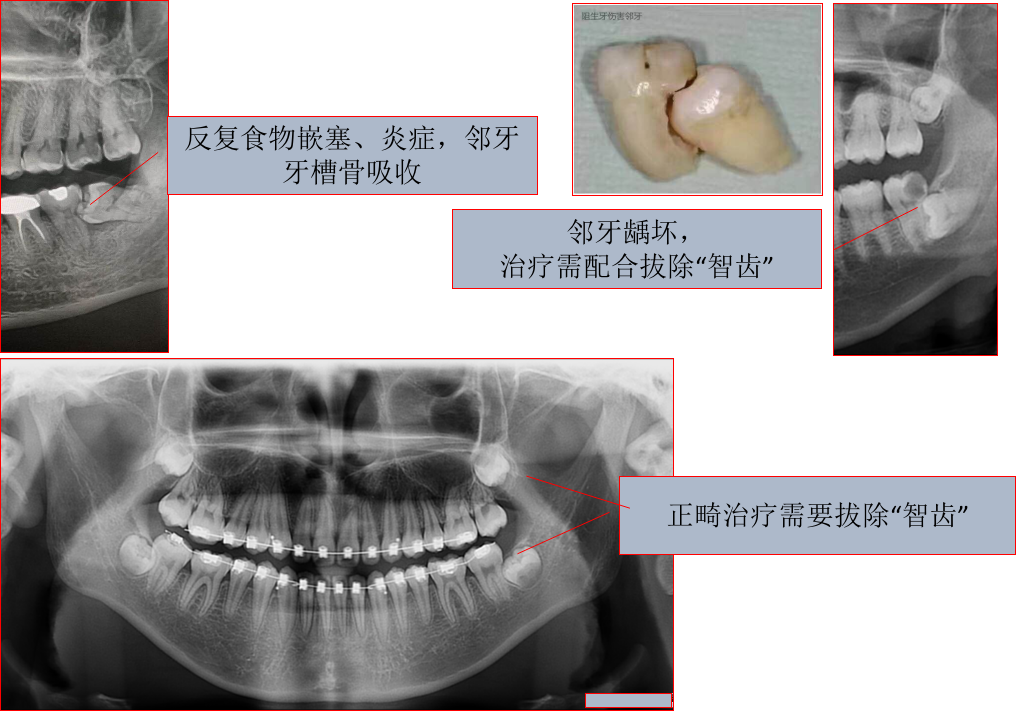

需要拔除的智齿主要分为三类:

第一类是已经有病变的,比如龋坏、冠周炎;

第二类是对邻牙造成影响的,比如向前或者水平方向阻生,和第二磨牙之间的食物嵌塞;

第三类是配合其它治疗的需要,比如正畸治疗、修复治疗的要求。

每位患者的情况都是不同的,但一般情况下,如果口腔中出现以下变化,智齿则很可能需要被拔除:1.疼痛2.感染3.囊肿4.肿瘤5.损坏邻牙6.牙龈疾病7.龋齿8.作为正畸或其他牙科治疗的一部分,牙医/口腔医生也可能建议拔除智齿。

在做任何决定之前,口腔医生会口腔检查,并做X光检查。您可以和口腔医生一起讨论最好的治疗方式。